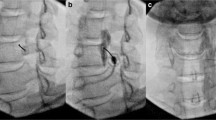

Each patient received two LSB treatments in a month in accordance with our standard protocol. NRS scores and lower extremity SSR of patients were recorded before enrollment and then recorded again 1 week after the second LSB treatment. Throughout the procedure and for at least 30 min later, the patients were continuously monitored by continuous noninvasive blood pressure monitoring and pulse oximetry. Just prior to the LSB, an intravenous line was established for safety purposes. Physicians with considerable experience performed the LSB procedure on all CRPS participants in the trial. Based on the previous literature [9], each patient was lying on his side during the procedure. By combining ultrasonography and fluoroscopy, the target of LSB was located in the upper third of L3 or the lower third of L2. A 15-cm, 20-gauge needle was inserted with real-time ultrasound guidance until the anterolateral side of the vertebra was reached after needle insertion. The anterior fascia of the psoas major muscle was penetrated by the ultrasound through guidance medially over the transverse process of the lumbar spine. The psoas major muscle on the anterolateral side of the lumbar vertebral body was the target of the needle tip, which was positioned anteriorly and medially. To avoid harming the vascular system and to create the needle trajectory, color Doppler was used. Before placing the needle, the kidney was examined to ensure that it would not get in the way. Using an in-plane technique, the needle was inserted from the lateral to the medial direction. After confirming the final position of the needle tip, the injection of 2–3 ml of contrast agent was then monitored using the C-arm in the anterior posterior (AP) and lateral projection. In a successful LSB, the sympathetic diffusion of the contrast agent was straight throughout the longitudinal axis with no lateral or posterior extension and no apparent psoas shadow. Following the confirmation that the contrast dye had diffused appropriately, 15 ml of 1% lidocaine was injected [10].

The SSR test uses electrodiagnostic equipment (Focus, Dantec Keypoint) to monitor an induced change in the electrical potential of the skin to evaluate sudomotor function. Electrical stimulus was used to detect SSR in the lower extremities, with surface electrodes containing an active electrode and a reference electrode. In a room with a temperature of approximately 25 °C, the active potential changes were recorded on the soles of the feet, and the dorsum of the feet was used as a reference. The stimulus current has a wave width of 0.2 ms, a current intensity of 20–30 mA, and an interval of more than 60 s between electrical stimuli, which can minimize the inaccuracy caused by the adaptation of the stimulus site. The SSR parameters to be measured include latency (the time when the baseline deviates for the first time following an electrical stimulus) and amplitude (the distance between negative wave peak and positive wave peak) (Fig. 2). That SSR failure to export was defined as no reaction to the stimulus at either extremity; that is, no consistent change in the baseline was detected in either of the 2 s following the stimulus recordings. Finally, the last SSR test was conducted no less than 1 week after LSB treatment.